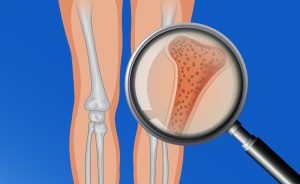

La articulación de la rodilla como tal, se compone de la unión del fémur y de la tibia. Como elementos estabilizadores de la rodilla encontramos la cápsula articular y los ligamentos; tanto los colaterales, medial y lateral así como los ligamentos cruzados que los encontramos internamente, en la parte posterior encontramos también el ligamento poplíteo. Como medio de amortiguación de la rodilla encontramos el cartílago articular y los meniscos. Estos son dos “discos” que se apoyan en el platillo tibial a nivel interno y externo y sirven de apoyo para los cóndilos femorales.

.- Pérdida de parte del cartílago articular por desgaste o degeneración del mismo.